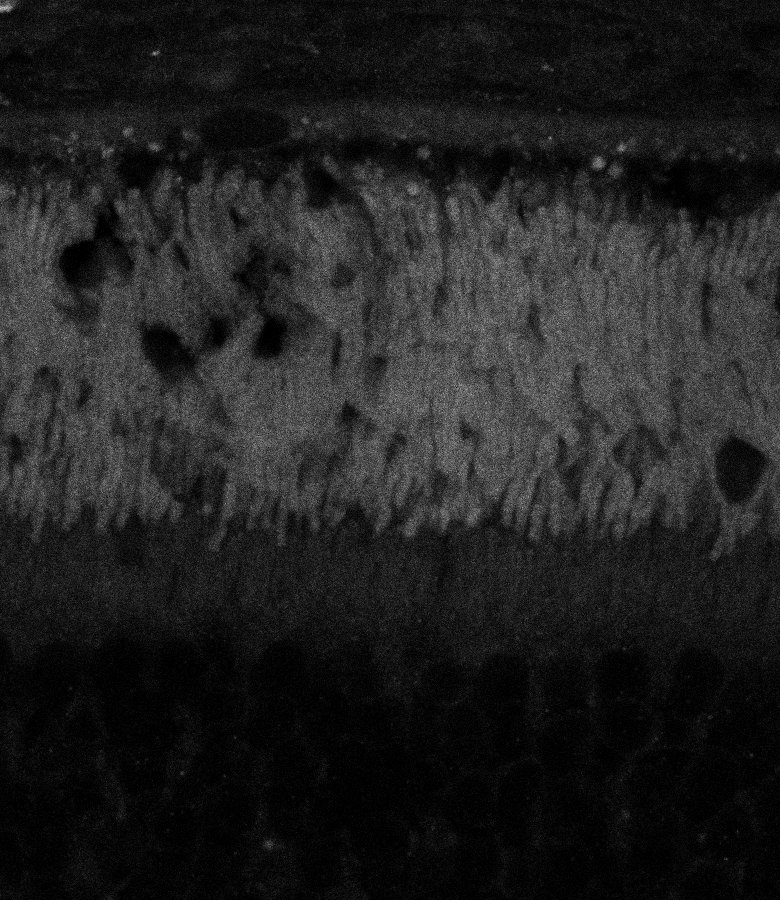

Tubulin

Tubulin - Bip

Tubulin - Nuc